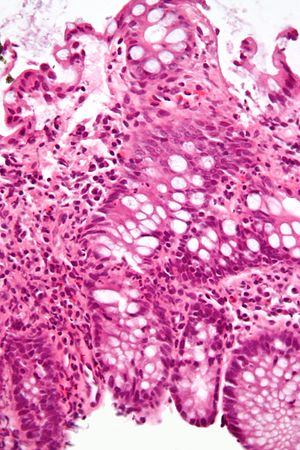

Micrograph showing inflammation of the large bowel in a case of inflammatory bowel disease. Colonic biopsy. H&E stain.